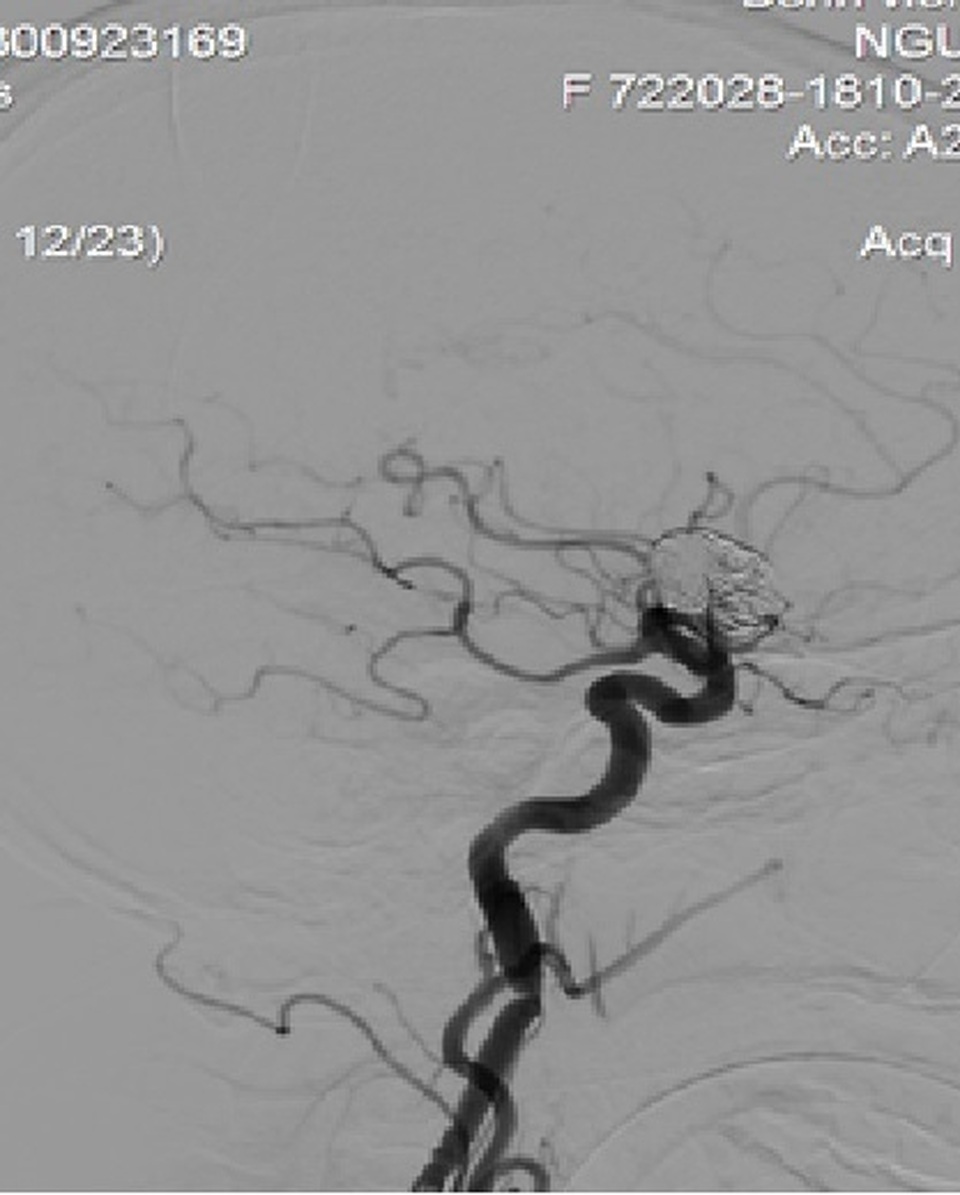

Hình ảnh túi phình đã tắc sau can thiệp, dòng chảy vào túi phình khổng lồ động mạch cảnh trong phải đã giảm gần hoàn toàn sau đặt stent chuyển dòng, khởi phát quá trình lấp dần để tắc túi phình hoàn toàn.

Sau can thiệp, bệnh nhân tỉnh, tiếp xúc tốt, huyết động ổn định, có thể xuất viện ngày hôm sau. Ê-kíp mổ được thực hiện với sự chỉ đạo và hỗ trợ của TS.BS. Nguyễn Trọng Tuyển (Bệnh viện Trung ương Quân đội 108), Th.s. Lê Vũ Huỳnh, Th.s. Nguyễn Viết Quý và ê-kíp can thiệp mạch não của Khoa Đột Quị, với sự gây mê của khoa Gây mê Hồi sức Tim mạch, Bệnh viện Trung ương Huế. Hiện bệnh nhân đang chờ để được xuất viện.